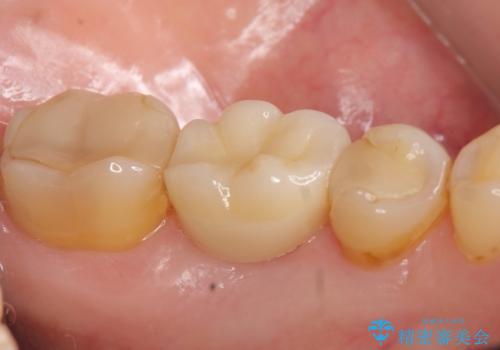

今回用いたオールセラミッククラウンはジルコニアフレームという白い素材の上にセラミックを盛っているため、審美性が非常に高いのが特徴です。

また、ジルコニアは人工ダイヤモンドの材料にも使われているほど高い強度を持っており、そのためオールセラミッククラウンは審美性だけでなく、奥歯やブリッジの補綴も可能とするクラウンです。